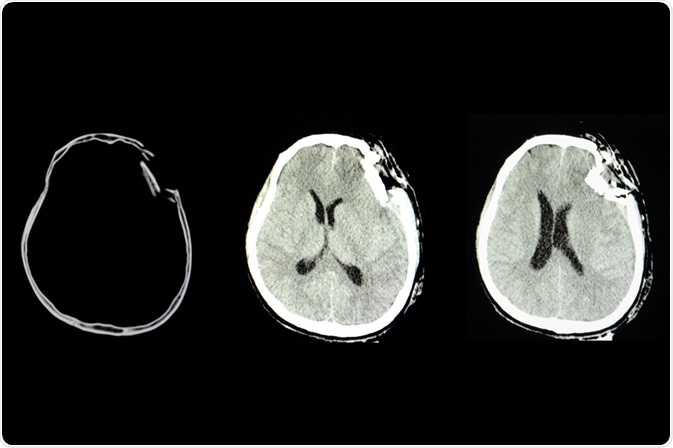

Traumatic brain injury (TBI) mainly occurs due to a sudden bump, blow, or jolt to the head, and the condition is associated with impairment in the brain’s normal activity. It is a leading cause of mortality or permanent disability in children.

In the new edition, four recommendations, which are graded as level III, are made to improve the efficacy of three types of monitoring systems: intracranial pressure monitoring, advanced cerebral monitoring, and neuroimaging (newly added).